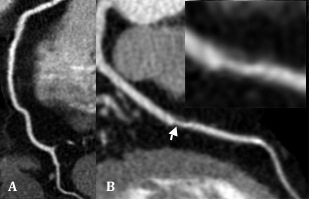

Während die RCA (A) völlig unauffällig zur Darstellung kommt, zeigt die LAD (B) im mittleren Drittel eine nicht-kalzifizierte Plaque (Pfeil und Insert).

© Universitätsklinik für Radiologie und Nuklearmedizin

72y, m, laut EKG St.p. nicht-rezentem MCI (Hinterwand)

Zuweisung zur CTA zum KHK-Nachweis bzw. zur Therapieplanung

Darstellung zahlreicher relevant stenosierender, teilweise verkalkter Läsionen im Verlauf der RCA (Pfeile). Passend zum EKG-Befund sowie zu den Läsionen im Verlauf der RCA ausgedehnte Narbe im Bereich der Hinterwand (Pfeilspitzen).